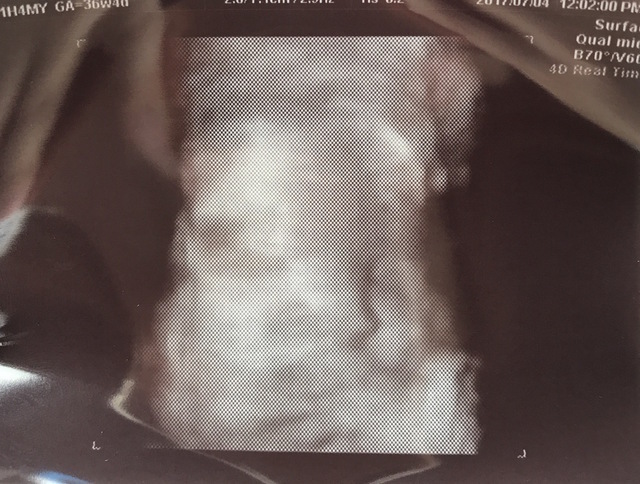

36週2日(36w2d・男の子)|kikilala さん(31歳)

エコー写真撮影時のエピソード:

なかなかお股を見せてくれず性別が間際までわかりませんでした。顔はよく見せてくれて、エコーの写真はこっちを向いています。

しかし、4Dエコーを撮るときだけは手で顔を隠していました(笑)恥ずかしがり屋さんなのかな?と病院の方と話しました。

やっと見せてくれた顔が私にそっくりで、うまれてきた顔も私にそっくりな息子です。